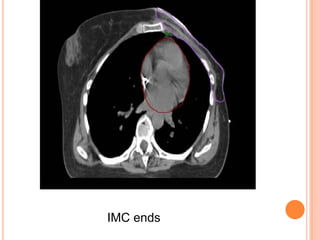

IMC ends